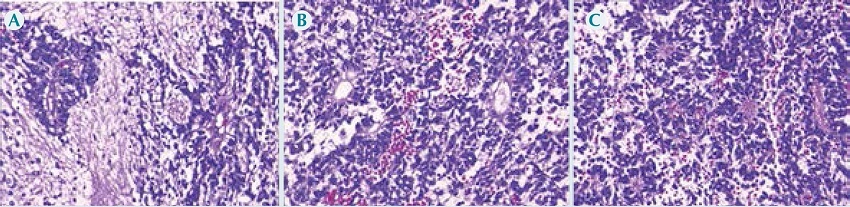

En el tejido tumoral analizado se observó una neoplasia maligna de estirpe glial compuesta de células con núcleos regulares, redondos a ovalados y abundante cromatina granular; entre los núcleos era evidente un fondo gliofibrilar variablemente denso; con mucha frecuencia se reconocían pseudo-rosetas perivasculares en las que las células tumorales estaban dispuestas alrededor de los vasos, con una zona intermedia que constaba de prolongaciones ependimarias finas dirigidas hacia la pared del vaso (Figura 3). Las células neoplásicas también formaban estructuras pseudo-glandulares redondas o alargadas (rosetas, conductos) que recuerdan el conducto ependimario embrionario, con prolongaciones largas y delicadas que se extendían dentro de una luz. Con los hallazgos histopatológicos de obvia diferenciación ependimaria en las áreas hipercelulares, pero sin actividad mitótica evidente, necrosis, ni proliferación vascular y que alternaba con áreas hipocelulares en donde predominaba el fondo gliofibrilar, la neoplasia fue diagnosticada como ependimoma celular grado II de acuerdo con la clasificación la Organización Mundial de la Salud.1